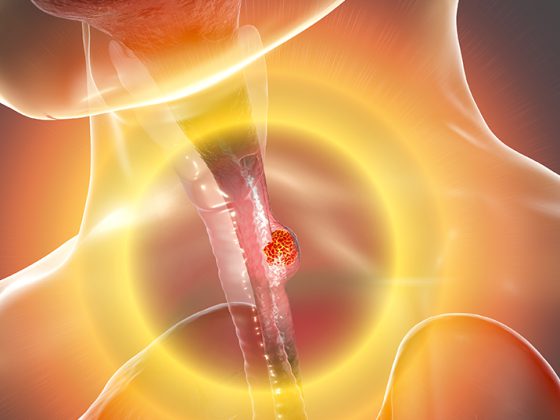

Forscher des Zentrums für Regenerative Therapien Dresden (CRTD) und der Medizinischen Fakultät der TU Dresden haben einen Signalweg identifiziert, der zur Darmentzündung beitragen kann. Sie zeigen, wie ein menschlicher Gendefekt die Anfälligkeit dafür fördert, dass Bakterien Entzündungen im Darm auslösen können. Ausgehend von dieser Erkenntnis berichten die Forscher von einem Potenzial für neue Therapeutika.